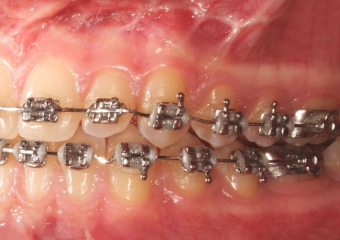

Mordida inicial - Clínica Cliniface

Mordida inicial